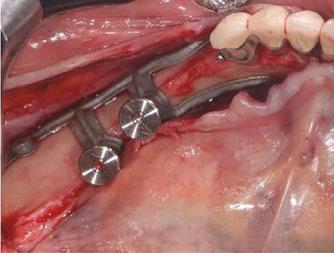

2. Surgical protocol

The procedure is performed under local anesthetic and lasts between 1 and 1-1/2 hours per side.

The first step is to raise a flap wide enough to allow adequate access to the surgical site. The crestal incision is made so as to evenly distribute the attached gingiva on either side of the future abutments. It extends to the anterior teeth via an intrasulcular incision and ends along the anterior edge of the ascending ramus.

The aim is to create full-thickness flaps to expose the chin foramen and protect the inferior alveolar pedicle (nerve) on the vestibular side. The detachment should then continue beyond the external oblique line to the basal margin of the mandible, then to the insertion of the buccinator muscle without detaching it.

On the lingual side, it is also important to push back the sublingual compartment by lifting, still in full thickness, to the medial oblique line posteriorly and apically up to the anterior digastric fossa, avoiding effraction of the mylohyoid muscle and mental spines (Figures 6 and 7).12

Some clinicians may choose to use a technique for one-piece subperiosteal implants. However, the author notes that one-piece bilateral subperiosteal implants are more difficult to insert, making surgery more complex. The surgery

Figure 8 (left): The Panthera SUB implant is gripped to facilitate insertion without damaging it. Figure 9 (right): Positioning the implant and checking its fit (occlusal view)

Figure 6 (left): Preoperative situation, panoramic radiograph and intraoral photo. Figure 7 (right): Incisions and flap detachment